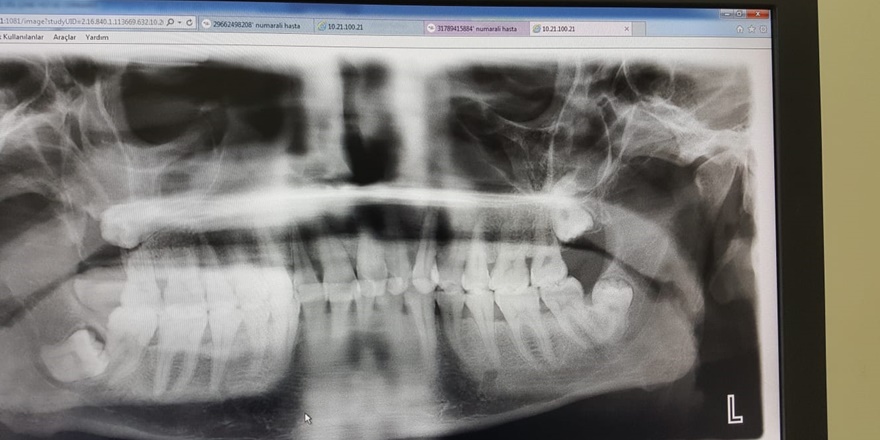

Diyarbakır’da tedavi olmak için birçok sağlık merkezine gittiğini belirten Yikitlar, “Diyarbakır ‘da gitmediğim doktor kalmadı tedavi etmediler hepsi beni Dicle Üniversitesi Çene Cerrahına sevk ettiler yapsa yapsa orası yapar dediler. Ben de gittim. Dediler senin burada tedavini yapamayız, senin ancak İstanbul ya da Ankara gibi büyük şehirlere gitmen lazım burada yeterli ekipman yok . Tedavi etmediler şu an yüzümde kist oluştu iltihabım her yere dağıldı sağ tarafta tat ve sağ burnum iltihap tarafından kapalı şu an” şeklinde konuştu.